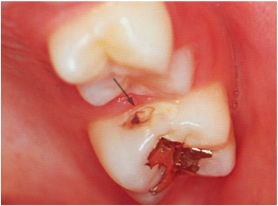

さらに、6歳臼歯で多いのが、写真のような歯と歯の間にできたムシ歯。

乳歯が抜けるとハッキリ解りますし、抜けてすぐに処置すれば、歯を削る量は最小限に止められます。

予防処置だけでなく、早期発見早期治療も、普段のマメな通院があってこそなのです。